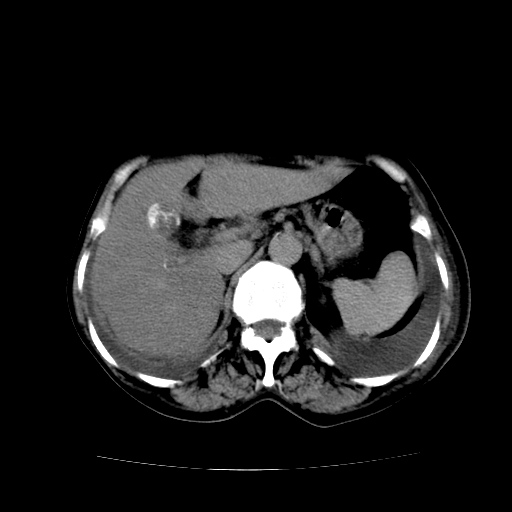

女70y乳腺ca(针吸活检)

多部位转移瘤的诊断可以肯定,我的疑问是:双肺对称高密度影及胸水是否为心衰肺水肿,病人体虚弱,不好意思图象传的乱![em9]

肺部病变为淋巴转移,肝脏转移,及局部淋巴转移。胸水可能为淋巴回流受阻(血性的考虑胸膜转移)

癌性淋巴管炎,肝脏转移,瓷胆囊

1)左侧乳腺癌并左侧腋窝及纵隔淋巴结转移,两肺淋巴道转移(癌性淋巴管炎),肝脏多发性转移。2)双侧胸腔积液。3)慢性胆囊炎。

5、肝转移瘤;

6、瓷胆囊。